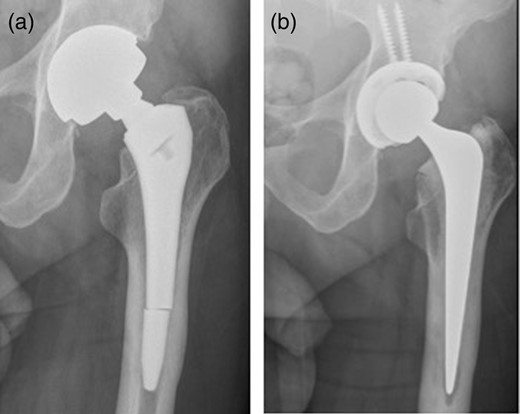

An 83-year-old female presented to our MoM for a routine review. Fourteen years previously, she had undergone a bipolar hemi-arthroplasties with a Furlong hip system (JRI limited UK). The bipolar hemi-arthroplasties was revised 6 years previously due to increasing hip pain and protrusion. At revision to THR, an R3 acetabular cup with a metal liner (Smith & Nephew, UK) was used retaining the primary stem. She described a 2-month history of a significant increase in pain over her right hip. There was no history of trauma or fall. X-rays showed a fracture through the stem of her right femoral component with radiolucent line in Zones 1, 2, 6 and 7 (Fig. 2a). She was admitted from the clinic and right hip was revised with ceramic on polyethylene bearing using Exeter stem and Trident cup (Stryker UK Limited; Fig. 2b).

(a) Fracture through the stem of right femoral component. (b) Post-revision X-ray.